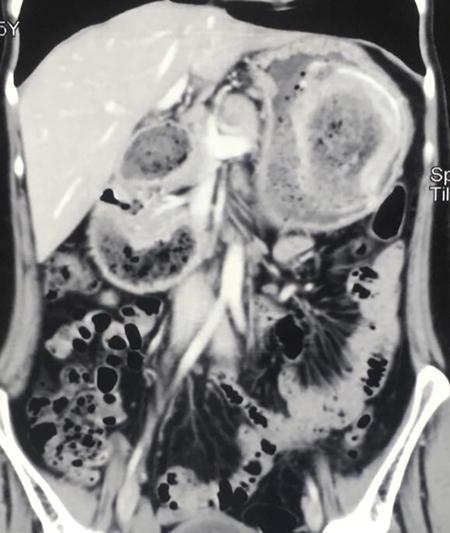

Fifty-year-old lady with vague upper abdominal discomfort.

Single contrast barium study (Fig. 7.4.5.1), CECT (Figs. 7.4.5.2 and 7.4.5.3).

Observations

Barium study shows large filling defect in the antrum forming acute angles with the wall. Undulating contour is seen along greater curvature with ulceration of overlying mucosal irregularity.

CECT shows a large lobulated mass involving lesser curvature and antrum with marked wall thickening along distal greater curvature.

Diagnosis

Carcinoma stomach.